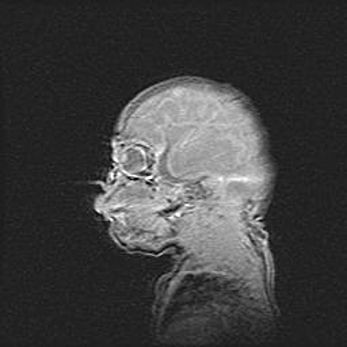

Открытая гидроцефалия.

Возраст: 9 месяцев 12 дней

Вес: 6800 г

Пол: мужской

Окружность головы: 41,5 см

Срок гестации: 28 недель

Гидроцефалия головного мозга у новорожденных имеет характерный признак: опережающий рост окружности головы приводит к визуально хорошо определяемой гидроцефальной форме сильно увеличенного в объёме черепа. Детские неврологи определяют следующие симптомы гидроцефалии у грудничков: выбухающий напряжённый родничок, частое запрокидывание головы, смещение глазных яблок к низу.